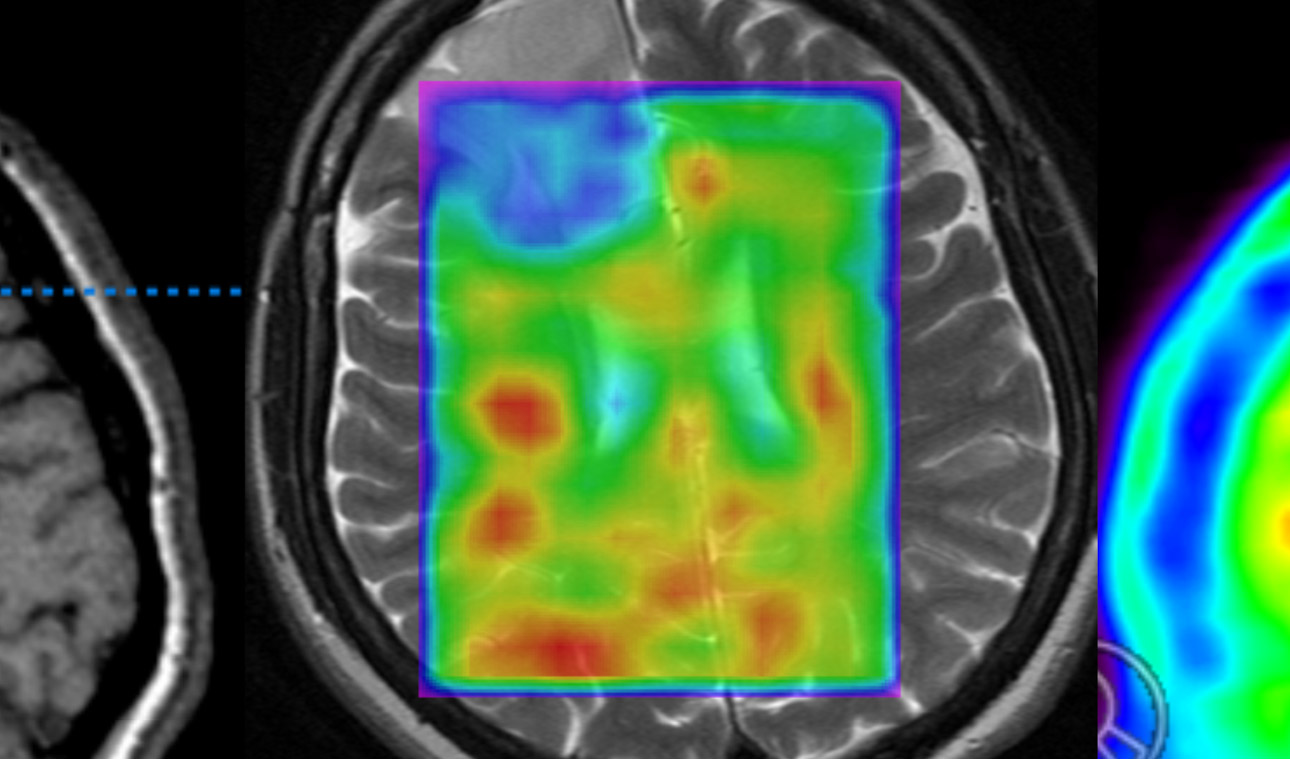

In enger Koordination mit den Nachbardisziplinen (Strahlentherapie, Onkologie, Neurologie, Neuroradiologie, Neuropathologie und auch Kinderheilkunde) bieten wir hier eine optimierte und umfassende Therapie für Patienten mit hirneigenen Tumoren und auch metastatischen Prozessen an....